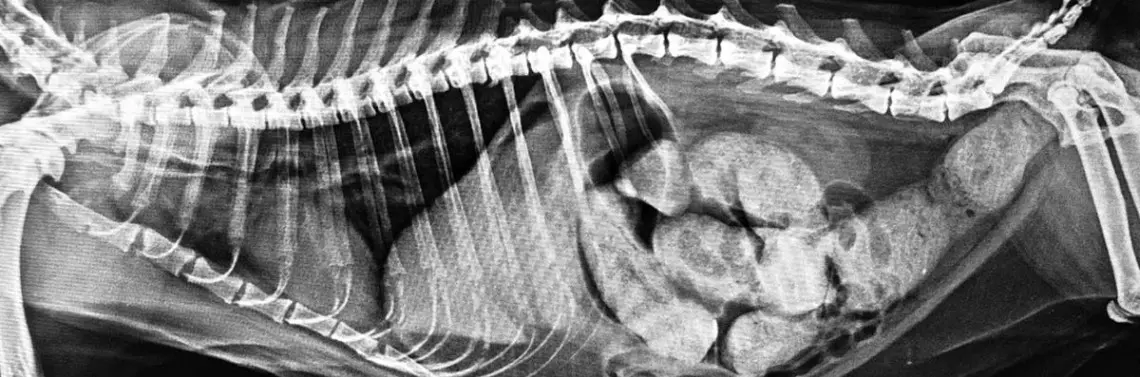

Skoro już ustaliliśmy, czym jest „ciocia Minnie”, należy również zaznaczyć, czym nie jest. Nie jest rozpoznaniem „szczęśliwego oka”, czyli ustaleniem diagnozy na podstawie pierwszej zauważonej zmiany. Nie jest to również rozpoznanie uniwersalne, czyli brak zmiany, która zwykle towarzyszy danej chorobie, nie wyklucza jej występowania. Pojęcie prawne o domniemanej niewinności oskarżonego nie ma w radiologii racji bytu! Wiele chorób ma obraz łudząco podobny do rozpoznania „cioci Minnie” innej choroby (Fot. 9A–B).

W rozumieniu rozpoznania „cioci Minnie” obraz zmian może odpowiadać jednej chorobie, natomiast to samo schorzenie może również przedstawiać się w inny sposób lub wręcz może nie być widoczne. Łatwym przykładem może być złamanie, ponieważ uwidocznienie złamanej kości oznacza jedną diagnozę, natomiast brak widocznego na radiogramie złamania nie może go wykluczyć, a jedynie zmniejszyć prawdopodobieństwo. Jednak nawet w ta...